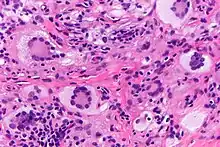

Histiocytic disorders like JXG are identified by the cells that make them up.[4] Immunohistochemical analysis is used to discern the immunoreactivity to certain antibodies in these analyses. JXG is a non-LHC disorder which is a varied group of disorders defined by the accumulation of histiocytes that do not meet criteria to be diagnosed as Langerhans cells. JXG is not metastatic and may be present with lipid deposits. JXG is often accompanied with other disorders such as neurofibromatosis type one and juvenile chronic myelogenous leukemia. Juvenile variety xanthogranuloma can be distinguished from xanthoma by the spread of the lesion and the lack of lipid abnormalities. Other similar diagnoses include molluscum contagiosum, hemangioma and neurofibroma.[4]